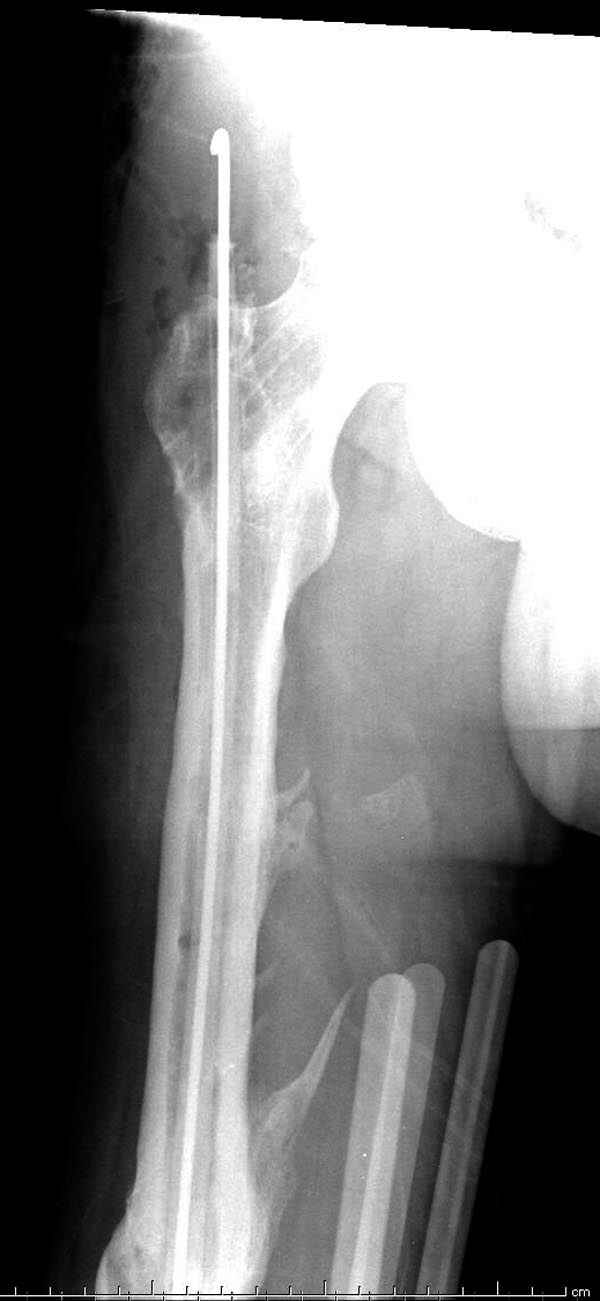

Инфекция канала и стрессовый перелом:

Представляю снимки больного с политравмой: леченного в другом мед.учреждении по поводу открытого перелома бедра, сперва аппаратом наружной фиксации, затем пластиной. Обратился к нам через 8 месяцев после удаления пластины с проблемой несросщего перелома бедренной кости, без клинических проявлении к инфицированию (не все снимки сохранены)

Рутинный интрамедуллярный остеосинтез с расверливанием и с фиксацией реконструктивным трокантерик штифтом (рис №1, №2),

если первые 4 месяца послеоперационного периода проходил без проблем, но на 5 месяце появились боли в дистальном отделе бедра и температура, т.е. симптомы медуллярного инфицирования (рис №3, №4).

Замена реконструктивного штифта “Custom made Nail” с антибиотиком (рис №5, №6),

после промывки канала с рассверливанием внутреннего кортекса, через 4 недели антибиотический штифт удалили, оспалителный процесс остановлен и бедро сросся.